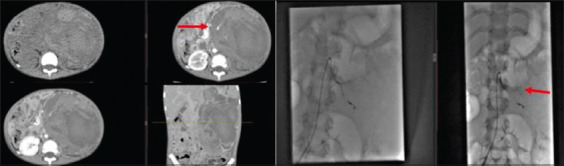

Case description: A previously healthy 5-year-old boy with no significant past medical or surgical history presented to the clinic with gradually worsening abdominal distension associated with occasional abdominal pain, gross hematuria, and lethargy for four months. Diagnostic investigations showed an 18-cm left-sided metastatic (pulmonary) renal tumor (Wilms), which was deemed unresectable on imaging. Treatment was planned according to the SIOP-RTSG protocol. However, he became hemodynamically and vitally unstable with acute, sudden distension of the abdomen on the left side after the first cycle of chemotherapy. Imaging showed active bleeding from an inferior branch of the left renal artery. Selective angioembolization was done, and chemotherapy was reinitiated with a patent left main renal artery. Following the fourth cycle of chemotherapy, he developed hemodynamic instability and abdominal pain; imaging revealed the resolution of pulmonary nodules and bleeding from the left renal artery (main); this was again embolized, and the patient was stabilized. The patient was operated on after optimization, and a complete resection of the mass was done with negative margins. On six months follow-up, he is well.